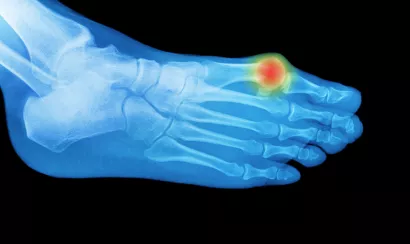

A quoi ressemble une crise de goutte typique ? « Une douleur très aigüe, très vive, très importante, présente jour et nuit, souvent au niveau du gros orteil. Celui-ci est alors gonflé, rouge violacé, très douloureux au toucher. La douleur dure quatre à cinq jours en moyenne puis disparaît toute seule. Un peu plus rapidement avec un traitement approprié », détaille le Pr Pierre Lafforgue, qui dirige le service de rhumatologie de l’hôpital Sainte-Marguerite, à Marseille. L’aspect d’une crise de goutte est souvent suffisamment typique pour porter le diagnostic, que confirmera la recherche d’hyperuricémie (excès d’acide urique) à l’occasion d’une prise de sang.

« Les crises se répètent à intervalle plus ou moins important, jusqu’à une année. Mais si elles ne sont pas soignées, elles se rapprochent, s’intensifient, touchent d’autres articulations. Jusqu’à un état de mal dit "goutteux", quasiment chronique, avec des douleurs articulaires permanentes. », précise le médecin. Il faut aussi noter qu’en période de crise aiguë, il est difficile de se chausser et de marcher à cause du gonflement douloureux du pied. D’où l’importance de dépister la goutte à un stade précoce.